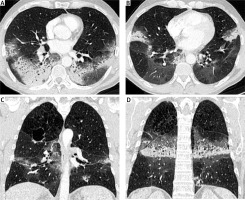

A 56-year-old man with stage IV non-small cell lung cancer (NSCLC) presented to the emergency department with progressive dyspnea and hypoxia. He had been diagnosed with adenocarcinoma of the right upper lobe 16 months earlier. PD-L1 expression in the tumor was 2%, and no other gene driver mutations were detected. The patient initially received treatment with a combination of platinum-based chemotherapy and immunotherapy (pembrolizumab). After the initial partial response to treatment, the patient remained in consolidation therapy treated only with pembrolizumab (Keytruda) for the last 12 months. At the time of the investigation of the progressive dyspnea, a chest radiograph and a computed tomography (CT) scan were performed. The chest radiograph showed bilateral airspace opacities consistent with either pneumonia or pneumonitis (Figure 1). The CT scan showed symmetrical bronchocentric consolidation with distribution suggestive of organizing pneumonia induced by pembrolizumab treatment (Figure 2). Bronchoalveolar lavage (BAL) was performed confirming the radiological diagnosis and excluding infection. The patient was treated with steroid therapy with clinical improvement and resolution of the symmetrical consolidation. Pembrolizumab (Keytruda) is a programmed cell death protein 1 inhibitor that is used as frontline treatment for NSCLC, with significant improvement of the survival rate [1]. Despite pembrolizumab’s clinical benefits, some patients develop associated immune-related adverse events (IRAE) including pneumonitis [2]. Immunotherapy-associated pneumonitis is a rare (3–6%) [3, 4] but severe complication characterized by focal or diffuse parenchymal inflammation. The time of onset of pneumonitis after administration of immunotherapy is variable [5]. Symptoms are often nonspecific, including dyspnea, cough, malaise and low-grade fever, requiring a high index of suspicion, whilst some patients may be asymptomatic [4]. As a result, diagnosis of immunotherapy-induced pneumonitis is usually achieved by excluding other potential causes. Clinically it is graded using the Common Terminology Criteria for Adverse Events (CTCAE) severity scale, which ranges from grade 1, asymptomatic, through to grade 5, where death occurs [6]. Diagnosis is based on appropriate history and suggestive radiological findings on CT scanning. The most common radiological features include ground glass opacities, interstitial reticulation, or bronchocentric consolidation suggestive of patterns of organizing pneumonia (OP), non-specific interstitial pneumonia (NSIP), diffuse alveolar damage (DAD) or hypersensitivity pneumonitis (HP) and reflecting the histological patterns of interstitial pneumonia [7–9]. Definitive diagnosis may require a combination of BAL and/or a biopsy. Treatment options include supportive therapy alone, oral or intravenous corticosteroids and cessation of immunotherapy [9].